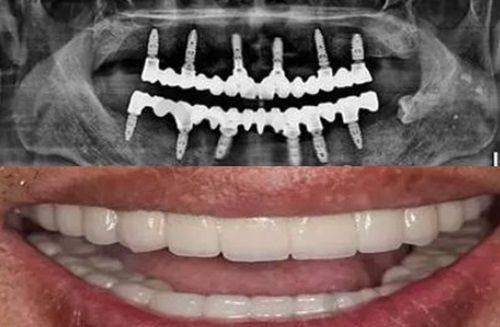

种植牙价格:蓝田县口腔医院种植牙价格是 4000 - 15000 元起一颗。其中,韩国种植牙价格 6000 元起一颗,是本地较便宜的种植牙品牌且使用人数较多;国产种植牙价格 4000 元起一颗;美国种植牙价格 7000 元起一颗;法国种植牙价格 8000 元起一颗;瑞士 ITI 种植牙价格 13000 元起一颗;瑞典诺贝尔种植牙价格 15000 元起一颗。